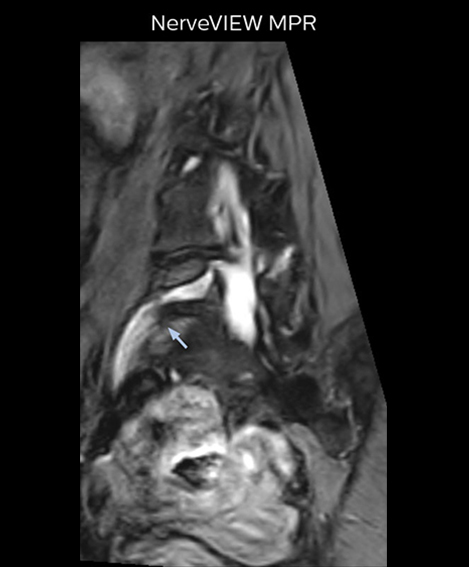

“For example, in sagittal images, when the presence of fat is observed in the intervertebral foramen, it suggests that there is a margin around the nerve. Similarly, the absence of fat indicates that the nerve is being compressed. So, we used to deduce nerve compression indirectly. With NerveVIEW, however, we can observe the condition of the nerves directly, regardless of the presence or absence of fat. We always prefer such direct observation of anatomy over having to make an inference about it.”

“Although symptoms of typical disc herniation and atypical hernia are very similar, the actual site of herniation is different. It is therefore important to characterize the nerve’s condition both inside and outside of the intervertebral foramina. “Conversely, if we see no abnormality in NerveVIEW, we can assume at least that there is no severe condition that requires surgery. Like this, it can help us avoid unnecessary surgery. NerveVIEW can have a tremendous impact in this way.”

“NerveVIEW is really useful for those cases where a nerve disorder is strongly suspected based on the clinical examination but our regular MRI images do not show any findings. These atypical herniations and spinal canal stenosis, occurring in 5% to 15% of the total lumbar herniation/stenosis cases are our main target when using NerveVIEW,” says Dr. Yabuki.

“The intra-luminal signal of veins, especially around the intervertebral space, can be suppressed well with NerveVIEW. As a result, we can easily observe the detailed nerve structure around the posterior ganglion,” he says. “This is why we use 3D NerveVIEW for intraforaminal stenosis and extraforaminal stenosis/herniation (lateral disc herniation). On the other hand, if herniation is suspected to exist inside the dorsal root ganglion (DRG), balanced TFE or ProSet-FFE is applied. NerveVIEW is not suitable for evaluating the median type of herniation.” The SE-EPI DWI-based method for MR neurography works well for large FOV exams like whole-body MRI, but focal examination of nerves is often limited by the attainable spatial resolution (both inplane and slice direction) and geometric distortion. “3D NerveVIEW achieves higher in-plane resolution – close to our other routine spine sequences – and the source images can be used instead of adding a fat-suppressed T2-weighted sequence,” Tanji says.

“NerveVIEW can clearly show nerve courses and presence of nerve compression. However, when multiple abnormalities are seen, it can still be hard to determine which nerve is causing the symptoms,” says Dr. Yabuki. “In our experience so far, we see abnormal findings on NerveVIEW in about 70% of elderly patients. As the pain is usually caused by only one nerve, we thus need to find the exact corresponding nerve.” “With a nerve root block, the patient's pain is improved by infiltration of local anesthesia directly around the nerve root considered to be responsible. Knowing such nerve root block findings prior to image interpretation, helps to easily recognize abnormal findings on NerveVIEW as well. In other words, without a priori knowledge, based on symptoms and/or nerve root block findings, we must be aware of the possibility of overdiagnosis.”